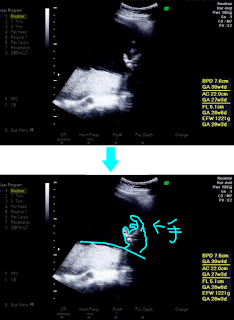

そして今日は第8回目の産婦人科検診の日♪

現在妊娠7ヶ月目、週数は27w1d☆お腹もだいぶ目立って来ました(*´ᴗ`*)

最近は赤ちゃんも大きくなって、エコー写真に映るのも体の一部とかになって来ました…

そして先生には前々から「男の子っぽい感じです」って言われていたのですが、今日ついに…私にも見えました!!

お、男の子のシンボルが(*´∀`*)!!笑

こうまでハッキリ写ったならこれはもう男の子でしょう✧